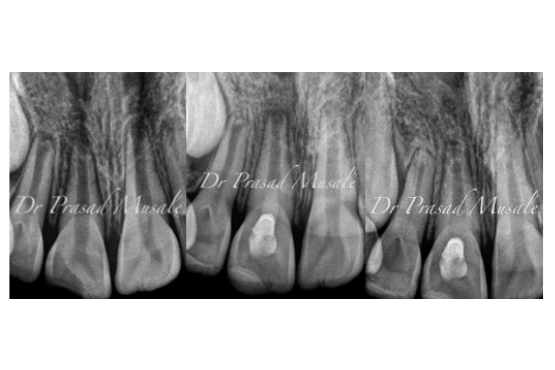

When your child’s cavity is deep and the pulp is dead inside, we remove the decay, clean the root canals and induce a bleeding within the tooth to restore blood supply to the tooth and promote root formation.